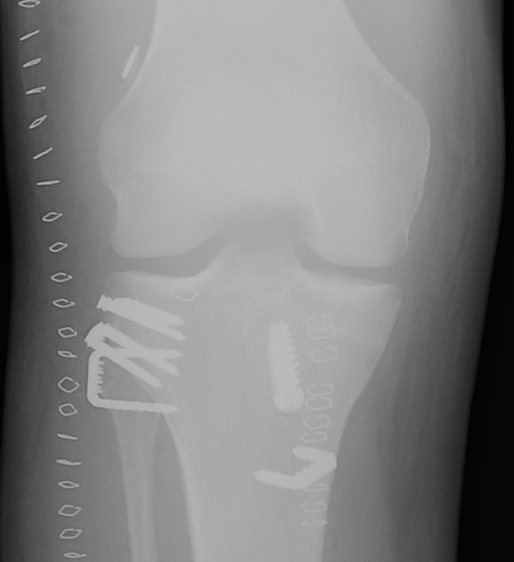

Xray following PCL reconstruction, LCL and politeus reconstruction. CT demonsrating popliteus and LCL tunnels